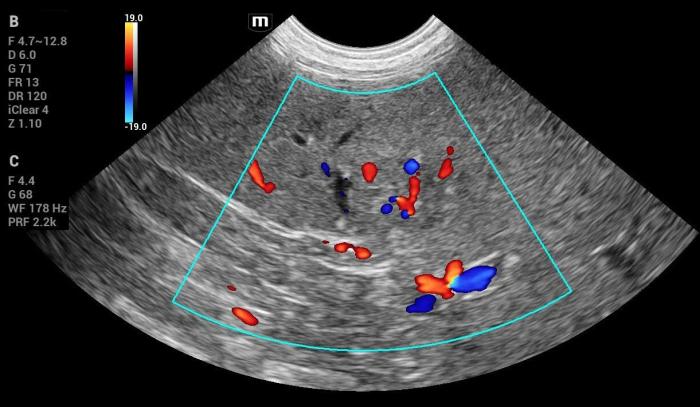

- Vascularización Doppler color positiva (Figura 18-19).

- Elastográficamente endurecida (aumento marcado de rigidez).

- Doppler positivo.

Hallazgos elastográficos (Natural Touch Elastography®): la lesión de mayor tamaño mostró rigidez elevada, significativamente superior al parénquima esplénico normal (Figura21-22).

Este comportamiento coincide con el patrón elastográfico típico de lesiones malignas descrito en la literatura5, donde los tumores esplénicos (incluyendo hemangiosarcoma) tienden a presentar velocidades de onda de corte superiores a las de lesiones benignas.

Las mediciones fueron técnicamente consistentes, sin artefactos respiratorios ni subcapsulares.